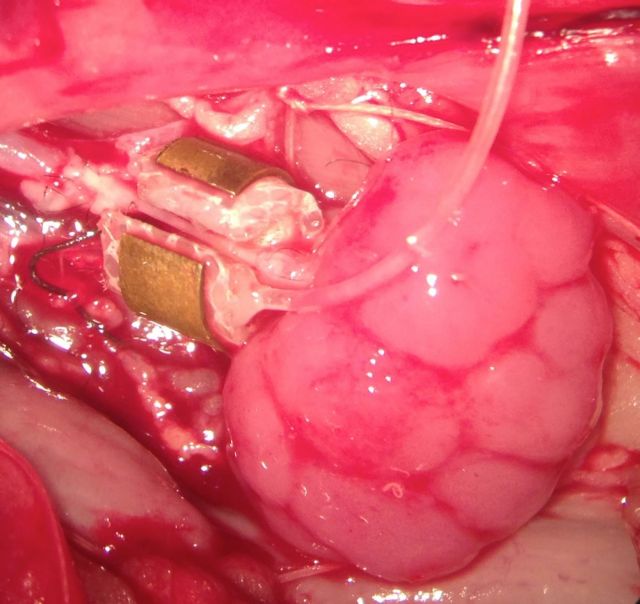

Οι ερευνητές διαβεβαιώνουν επίσης ότι η μελέτη εγκρίθηκε από επιτροπή Βιοηθικής της Ganongen, αποτελούμενη από δύο ανεξάρτητους χειρουργούς μεταμοσχεύσεων, δύο μέλη του κοινού που δεν συνδέονται με την εταιρεία και έναν γιατρό. Οι εμβρυακοί νεφροί μεταμοσχεύθηκαν σε ενήλικες αρουραίους των οποίων το ανοσοποιητικό σύστημα είχε εξουδετερωθεί ώστε να μην απορρίψει το μόσχευμα. Το όργανο συνδέθηκε με τα αιμοφόρα αγγεία του πειραματόζωου με μικροσκοπικά ράμματα, τέσσερις φορές λεπτότερα από μια ανθρώπινη τρίχα.

Το βασικό πρόβλημα που είχαν να αντιμετωπίσουν οι ερευνητές ήταν ότι η αρτηριακή πίεση των πειραματόζωων ήταν πολύ μεγαλύτερη από την πίεση σε ένα αναπτυσσόμενο έμβρυο. Τη λύση έδωσε μια συσκευή «ρυθμιστής αρτηριακής ροής», η οποία τοποθετήθηκε γύρω από τα αγγεία του αρουραίου για να περιορίσει τη ροή αίματος.